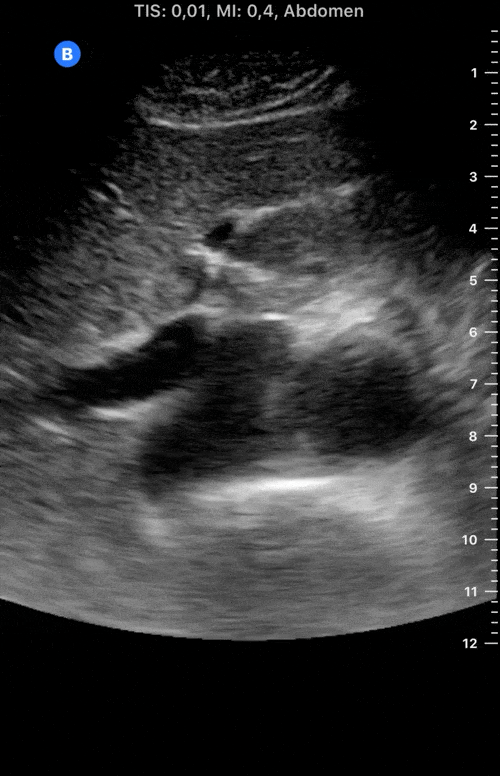

This is the standard window taught in FAST and might be the only one available during cardiopulmonary resuscitation (CPR). This view uses the liver as an acoustic window. To obtain good visualization is essential to handle the probe almost parallel to the anterior abdominal wall, trying to place it under the xiphoid process, pointing to the left shoulder. A deep inspiration or half inspiration can be useful to bring the heart closer to the probe and improve visualisation.

Remember that in the cardiac preset, the screen marking is on the right side. As a result, and unlike the FAST exam, the probe marking points towards the patient’s left. This view is used mainly to look for pericardial fluid, but it also provides information about ventricle size, chamber relationship and valvular abnormalities.